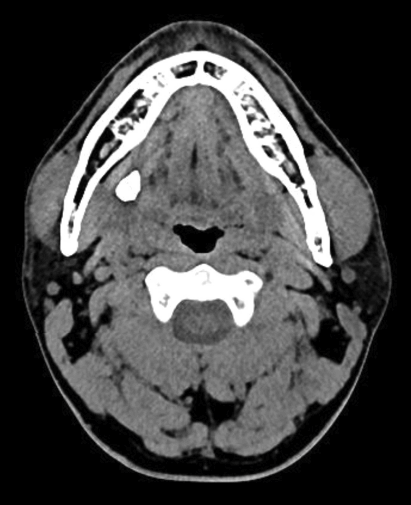

34세 남자 환자가 3개월 전부터 시작된 우측 악하선 부종 및 통증을 주소로 내원하였다. 환자의 증상은 식사시에 심해졌다가 시간이 지나면 호전되는 양상이었으며 내원 당시 이학적 검사상 우측 악하선 주위 부종 이외에 특이소견은 보이지 않았다. 외래에서 촬영한 경부 컴퓨터단층촬영 소견은 다음과 같았다. 이 질환에 대한 설명 중 틀린 것은?

③ 컴퓨터단층촬영시에 조영증강은 필요하지 않으나 종양과의 감별이 필요할 때는 시행한다.

③ 타석증을 진단할 때 컴퓨터단층촬영시에 조영증강은 필요하지 않으나 종양과의 감별이 필요할 때는 시행한다.